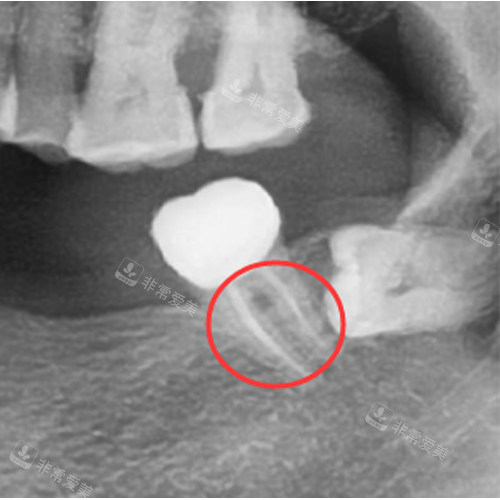

根管治疗后的牙齿

牙齿根部牙龈出血